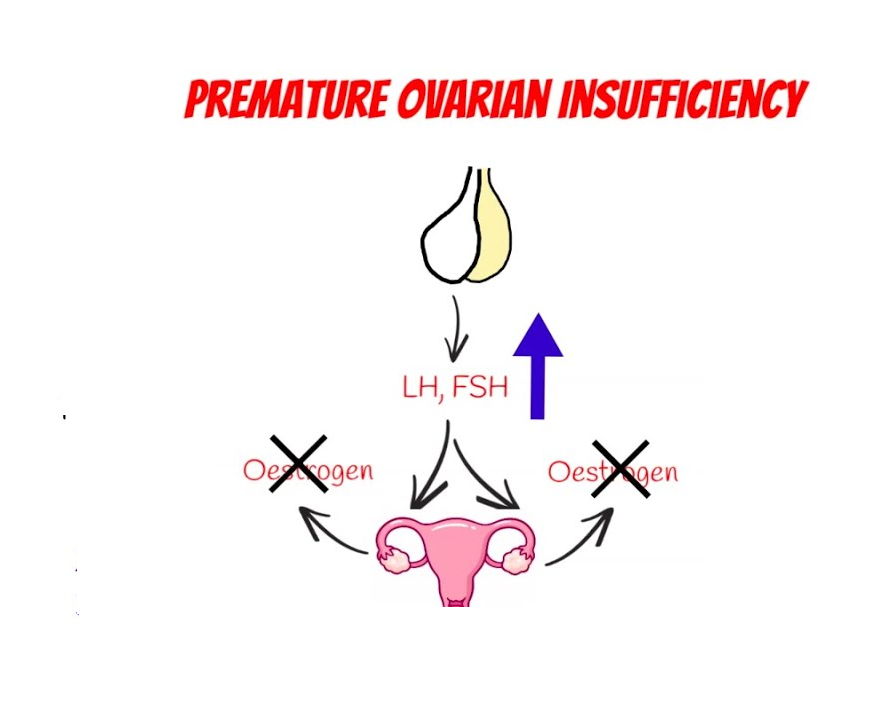

The Role of Hormones in POI

6.1 Estrogen and FSH

Estrogen is the main female hormone responsible for regulating the menstrual cycle, maintaining bone density, and supporting sexual health. Follicle-Stimulating Hormone (FSH) triggers the ovaries to produce mature eggs. In POI:

- Estrogen Levels drop due to reduced ovarian function.

- FSH Levels go up as the body tries to stimulate the ovaries to produce more eggs.

High FSH and low estrogen are strong indicators of POI and help doctors confirm a diagnosis.